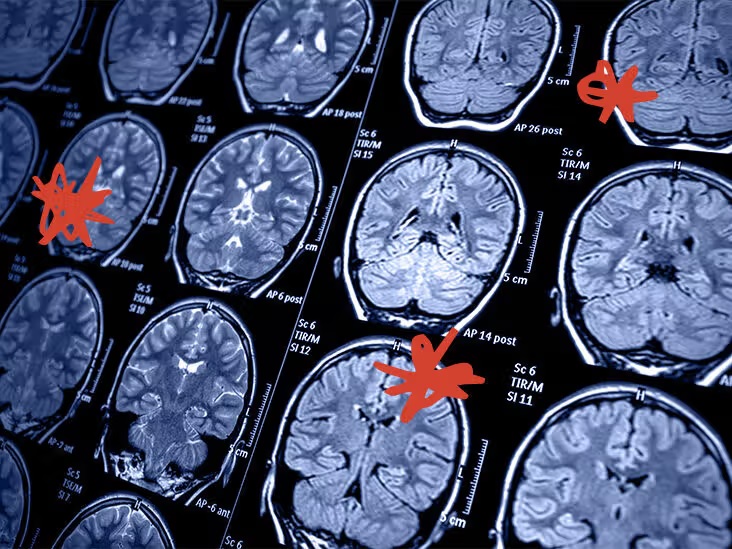

ਕੈਲੀਫੋਰਨੀਆ : ਕੈਲੀਫੋਰਨੀਆ ਯੂਨੀਵਰਸਿਟੀ ਲਾਸ ਏਂਜਲਸ ਦੇ ਖੋਜਕਰਤਾਵਾਂ ਨੇ ਇੱਕ ਨਵੀਂ ਨਵੀਂ ਦਵਾਈ ਵਿਕਸਤ ਕੀਤੀ ਹੈ ਜੋ ਸਟ੍ਰੋਕ ਰਿਕਵਰੀ ਨੂੰ ਹਮੇਸ਼ਾ ਲਈ ਬਦਲ ਸਕਦੀ ਹੈ। DDL 920 ਨਾਮਕ, ਇਹ ਦਵਾਈ ਲੰਬੇ ਸਮੇਂ ਦੀ ਸਰੀਰਕ ਥੈਰੇਪੀ ਦੀ ਲੋੜ ਤੋਂ ਬਿਨਾਂ ਮੋਟਰ ਫੰਕਸ਼ਨ ਨੂੰ ਪੂਰੀ ਤਰ੍ਹਾਂ ਬਹਾਲ ਕਰਨ ਵਾਲੀ ਪਹਿਲੀ ਦਵਾਈ ਹੈ।

UCLA ਦੇ ਨਿਊਰੋਲੋਜੀ ਵਿਭਾਗ ਦੇ ਚੇਅਰਪਰਸਨ ਅਤੇ ਮੁੱਖ ਖੋਜਕਰਤਾ ਡਾ. ਥਾਮਸ ਕਾਰਮਾਈਕਲ ਨੇ ਕਿਹਾ ਕਿ ਇਹ ਦਵਾਈ ਸਟ੍ਰੋਕ ਮਗਰੋਂ ਠੀਕ ਹੋਣ ਲਈ ਇੱਕ ਨਵੇਂ ਯੁੱਗ ਦੀ ਨਿਸ਼ਾਨਦੇਹੀ ਕਰੇਗੀ, ਜੋ ਕਿ ਰਵਾਇਤੀ ਥੈਰੇਪੀ ਦੀ ਬਜਾਏ ਅਣੂ ਦਵਾਈ ਵਾਂਗ ਕੰਮ ਕਰਦੀ ਹੈ। ਚੂਹਿਆਂ 'ਤੇ ਕੀਤੇ ਗਏ ਅਜ਼ਮਾਇਸ਼ਾਂ ਵਿੱਚ, DDL 920 ਨੇ ਦਿਮਾਗ ਦੇ ਨੁਕਸਾਨ ਦੀ ਸਫਲਤਾਪੂਰਵਕ ਮੁਰੰਮਤ ਕੀਤੀ ਅਤੇ ਗੁਆਚੇ ਹੋਏ ਨਿਊਰਲ ਕਨੈਕਸ਼ਨਾਂ ਨੂੰ ਬਹਾਲ ਕੀਤਾ। ਟੀਮ ਹੁਣ ਮਨੁੱਖੀ ਟੈਸਟਿੰਗ ਸ਼ੁਰੂ ਕਰਨ ਦੀ ਤਿਆਰੀ ਕਰ ਰਹੀ ਹੈ।

ਹਰ ਸਾਲ, ਸਟ੍ਰੋਕ ਦੁਨੀਆ ਭਰ ਵਿੱਚ 15 ਮਿਲੀਅਨ ਤੋਂ ਵੱਧ ਲੋਕਾਂ ਨੂੰ ਪ੍ਰਭਾਵਿਤ ਕਰਦੇ ਹਨ ਅਤੇ ਬਹੁਤ ਸਾਰੇ ਬਚੇ ਹੋਏ ਲੋਕ ਲੰਬੇ ਸਮੇਂ ਦੀ ਸਰੀਰਕ ਕਮਜ਼ੋਰੀ ਨਾਲ ਜਿਊਂਦੇ ਹਨ। ਮੌਜੂਦਾ ਇਲਾਜ ਮੁੱਖ ਤੌਰ 'ਤੇ ਹੋਰ ਸਟ੍ਰੋਕ ਨੂੰ ਰੋਕਣ ਅਤੇ ਜੀਵਨ ਦੀ ਗੁਣਵੱਤਾ ਨੂੰ ਬਿਹਤਰ ਬਣਾਉਣ 'ਤੇ ਕੇਂਦ੍ਰਿਤ ਕਰਦੇ ਹਨ ਪਰ ਕੋਈ ਵੀ ਪਹਿਲਾਂ ਹੀ ਹੋਏ ਨੁਕਸਾਨ ਨੂੰ ਸਿੱਧੇ ਤੌਰ 'ਤੇ ਉਲਟਾ ਨਹੀਂ ਦਿੰਦਾ। ਹਾਲਾਂਕਿ ਦਵਾਈ ਅਜੇ ਵੀ ਆਪਣੇ ਸ਼ੁਰੂਆਤੀ ਪੜਾਵਾਂ ਵਿੱਚ ਹੈ, ਇਸਦੀ ਸੰਭਾਵਨਾ ਨੇ ਪਹਿਲਾਂ ਹੀ ਡਾਕਟਰੀ ਭਾਈਚਾਰੇ ਵਿੱਚ ਉਤਸ਼ਾਹ ਪੈਦਾ ਕਰ ਦਿੱਤਾ ਹੈ।

ਮਾਹਿਰਾਂ ਦਾ ਮੰਨਣਾ ਹੈ ਕਿ ਇਹ ਨਾ ਸਿਰਫ਼ ਸਟ੍ਰੋਕ ਤੋਂ ਠੀਕ ਹੋਣ ਦੇ ਤਰੀਕੇ ਨੂੰ ਬਦਲ ਸਕਦਾ ਹੈ, ਸਗੋਂ ਭਵਿੱਖ ਵਿੱਚ ਦਿਮਾਗ ਦੀਆਂ ਹੋਰ ਸੱਟਾਂ ਅਤੇ ਡੀਜਨਰੇਟਿਵ ਸਥਿਤੀਆਂ ਨੂੰ ਵੀ ਬਦਲ ਸਕਦਾ ਹੈ।